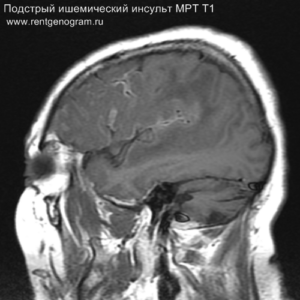

- подострая фаза (с 24 часов до 6 недель – накопление контрастного вещества)

Подострая фаза (24 часа — 6 недель)

На подостром этапе происходит разрушение гематоэнцефалического барьера, что приводит к вазогенному отеку, увеличивая объем ишемического инфаркта, возникновение масс-эффекта и возможного вклинения в случае обширного поражения (например, вклинение поясной извилины под фалькс или миндалин мозжечка в большое затылочное отверстие).

Разрушение гематоэнцефалического барьера (ГЭБ) приводит к накоплению контрастного вещества в области ишемического инсульта, используя технику контрастирования по «гиральному типу».

Когда в мозговых артериях происходит реканализация кровотока, это может привести к образованию геморрагических пропитываний и кровоизлияний («красный компонент» ишемического инфаркта), что будет отображаться на МРТ как ↑ на Т1 и Т2*, а на КТ — как участки с гетерогенной повышенной плотностью. На более поздних этапах подострой стадии наблюдается нормализация ранее повышенных показателей DWI и ADC, известная как «псевдонормализация» диффузии.